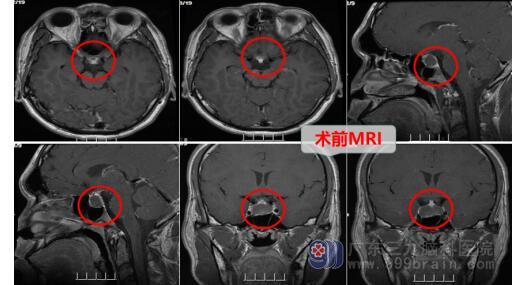

21岁的钟先生近两周出现头痛、头晕及呕吐,视力变得模糊,他意识到问题的严重性,在家人的陪同下在某医院行头颅检查, 结果显示鞍区占位性病变,考虑Rathke’s 囊肿。为了寻求更专业的治疗,钟先生在朋友的介绍下来到广东三九脑科医院神经外十科。接诊医生邓心情详细询问病史后,给予完善影像检查,头颅MR检查结果证实: 鞍区占位性病变,考虑Rathke’s 囊肿。

确定了病因所在,神经外十科医生团队对治疗方案、手术方案及要点进行详细的讨论及分析,选择行内镜下经鼻蝶鞍区Rathke’S囊肿切开引流术,手术顺利。术中垂体及视神经等保护良好。术后患者视力良好同前,头痛症状消失,无尿崩,无脑脊液漏等,术后CT显示病变切除彻底。